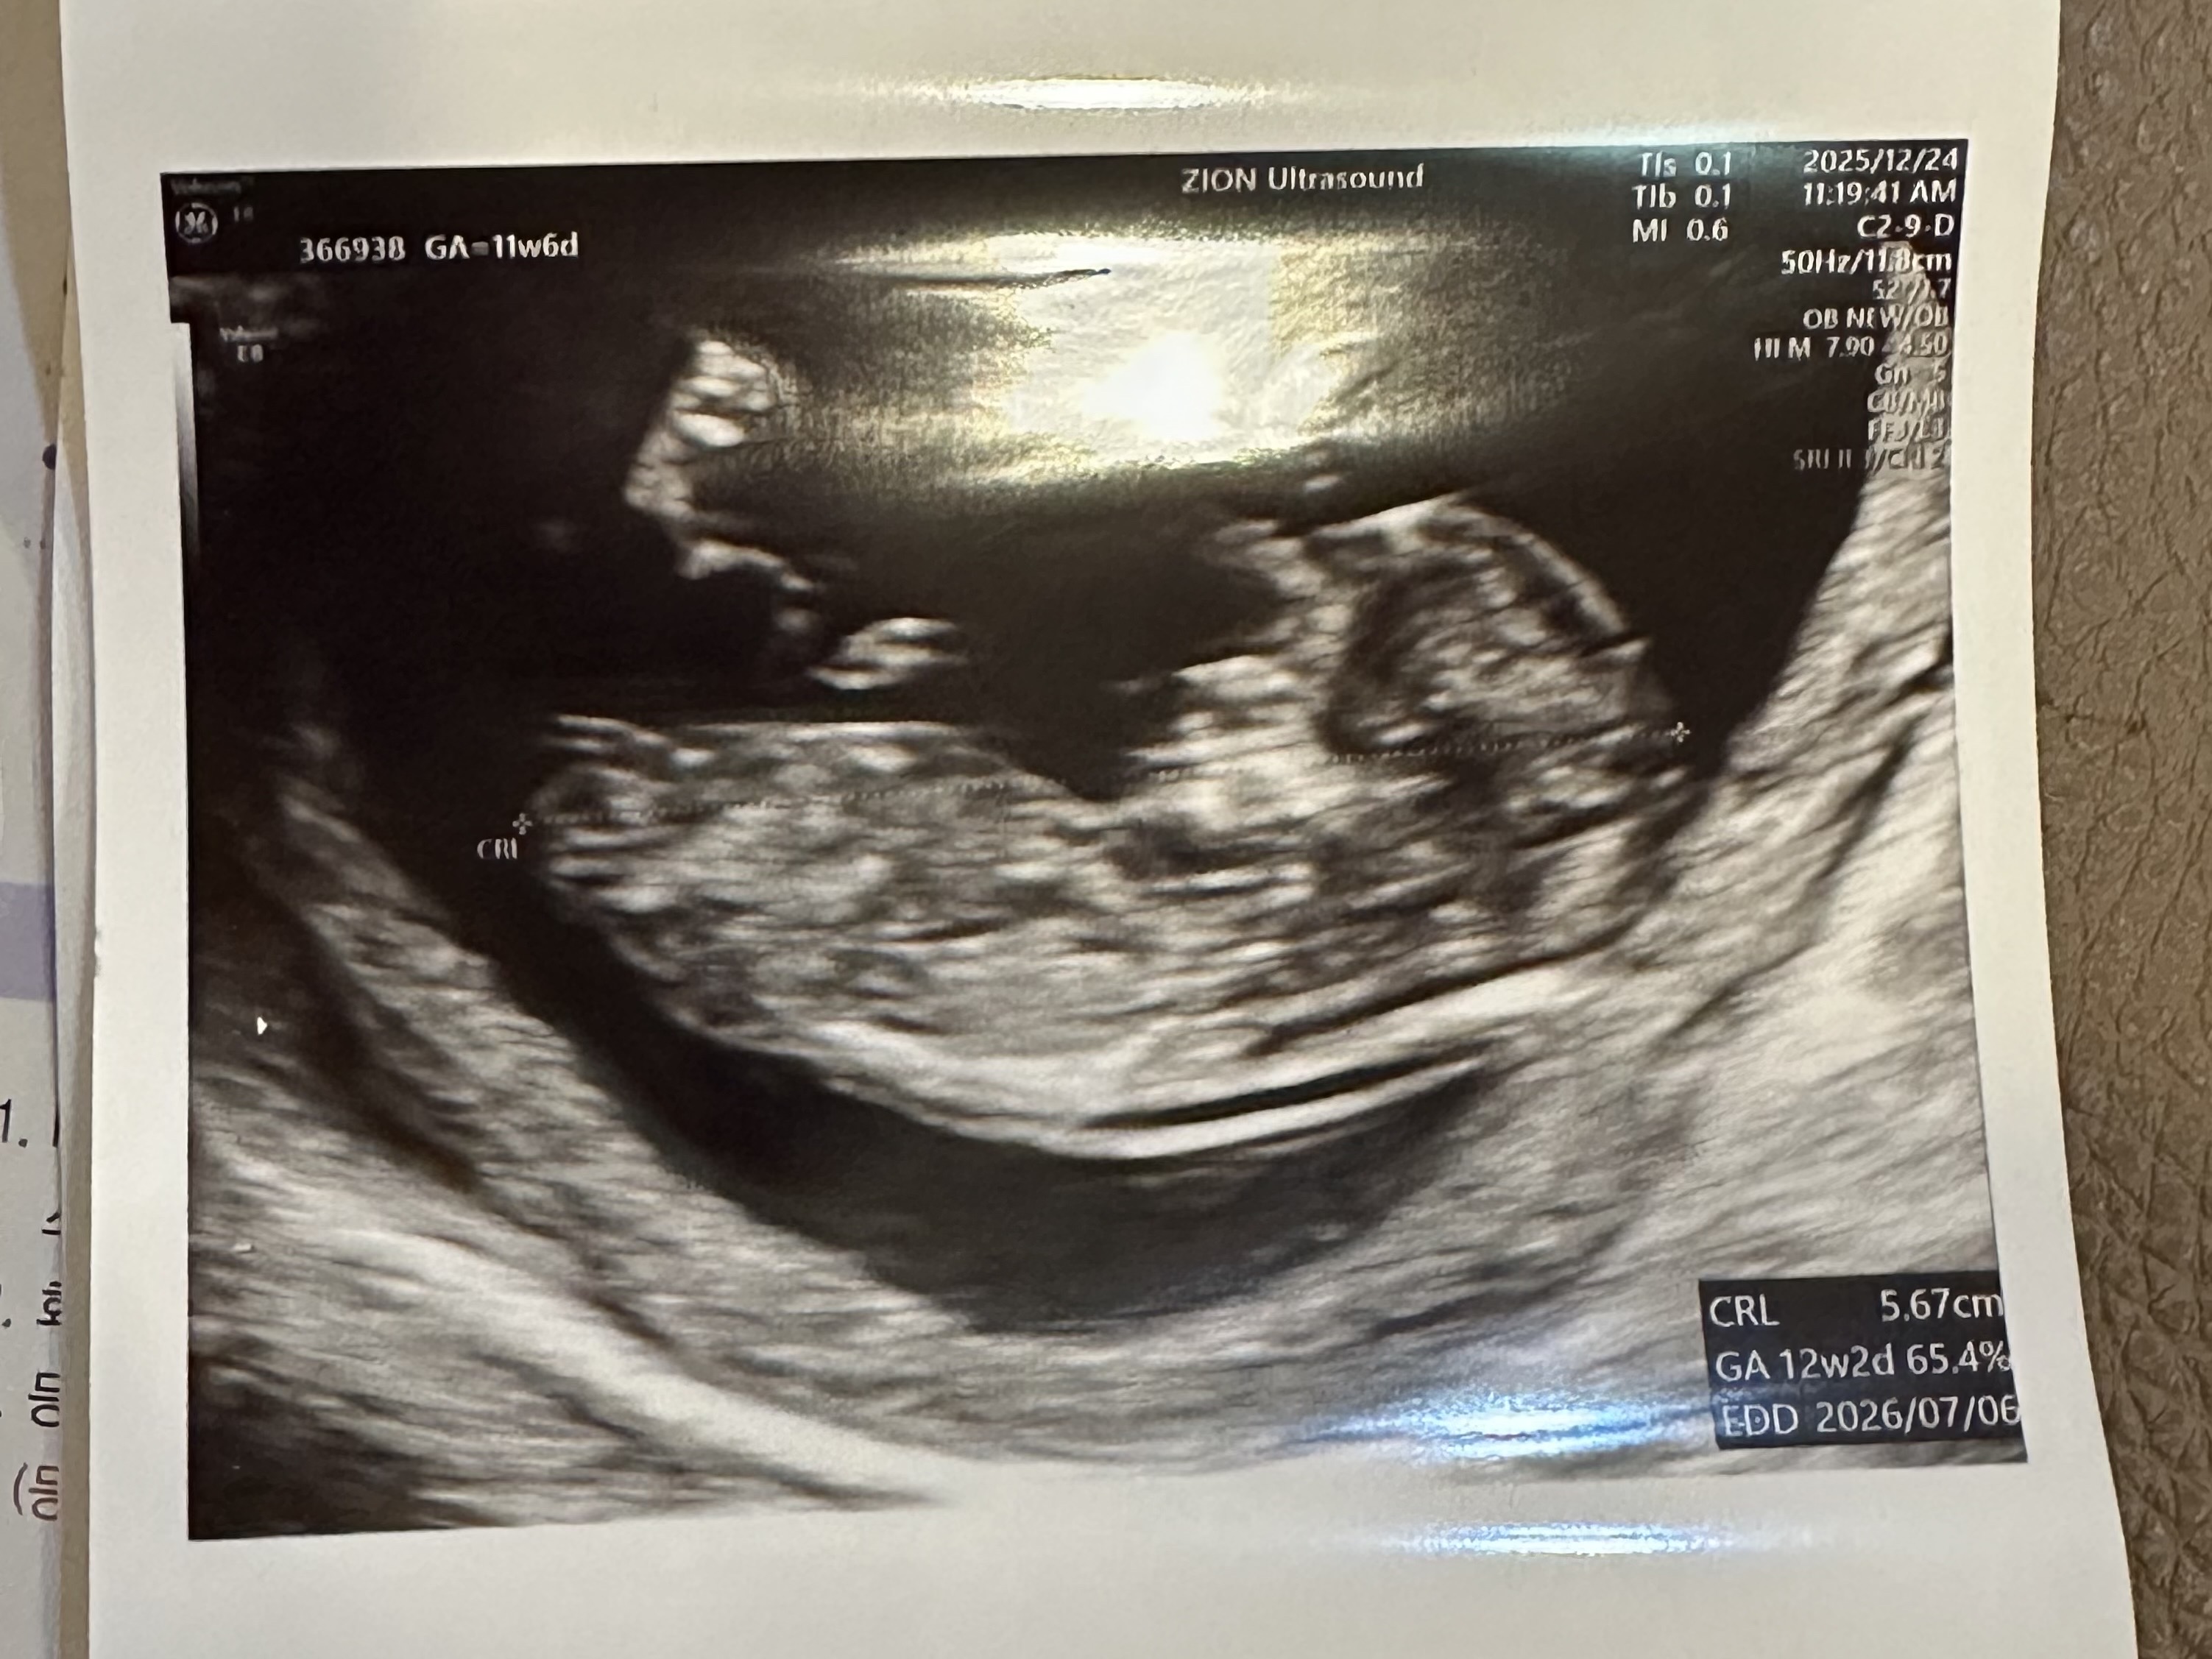

딸이요!

2026년 7월 베동

첫찌 아들 둔 둘째맘인데... 각도법 정확도가 70%나 된다길래 첨으로 여쭤봅니당!!! 딸일까유.. 아들일까유..